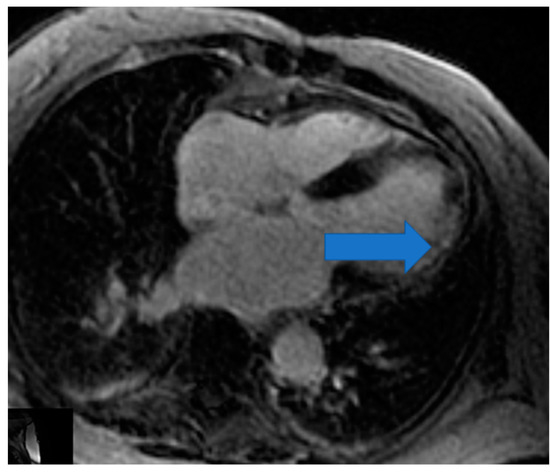

4.1. Biventricular Function Assessment

- Mavrogeni, S.; Pepe, A.; Nijveldt, R.; Ntusi, N.; Sierra-Galan, L.M.; Bratis, K.; Wei, J.; Mukherjee, M.; Markousis-Mavrogenis, G.; Gargani, L.; et al. Cardiovascular magnetic resonance in autoimmune rheumatic diseases: A clinical consensus document by the European Association of Cardiovascular Imaging. Eur. Heart J. Cardiovasc. Imaging 2022, 23, e308–e322. [Google Scholar] [CrossRef]